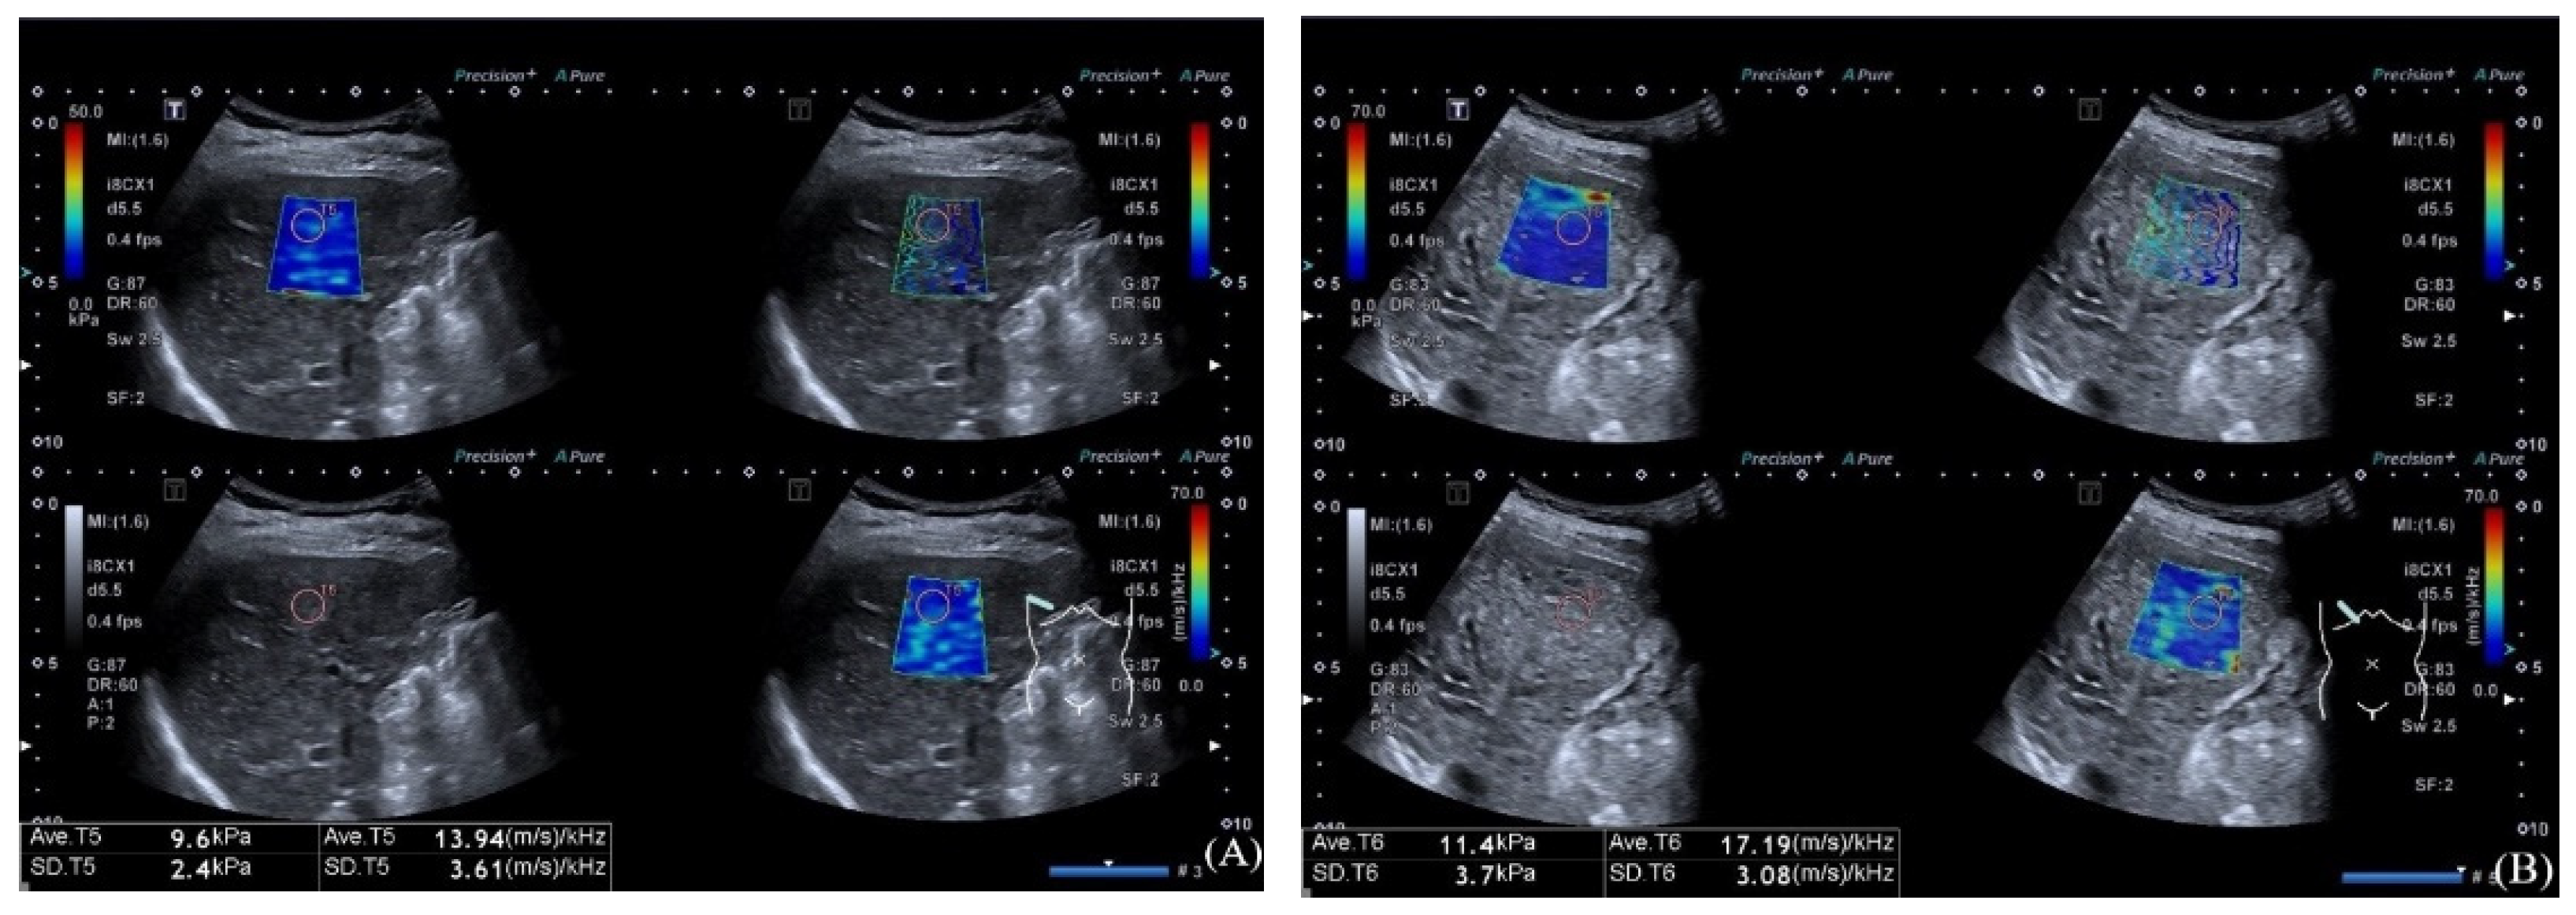

2.2. Ultrasound Examination

| SWDS (m/s/kHz) | 15.17 ± 1.88 | 17.04 ± 1.45 | −4.062 | <0.001 | 2.234 (1.267–3.941) | 0.005 |